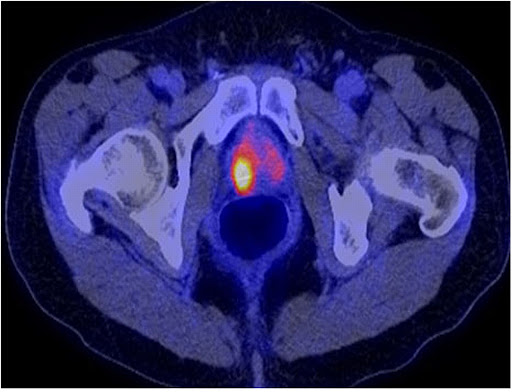

La aplicación tiene como objetivo mejorar el cribado y la detección precoz de posibles focos tumorales en la próstata, precisando en su estadificación, implementándolo en una herramienta ágil desde el punto de vista clínico con una alta capacidad de discriminación entre sujetos con y sin infiltración tumoral. Esto podrá hacerse combinando la información obtenida a partir de una analítica en sangre (Antígeno Prostático Específico, PSA), la imagen de diagnóstico PET/RM y la histología (biopsia o prostatectomía, Escala Gleason).

- La cuantificación convencional que realiza el equipo de PET/RM.

- Las características radiómicas extraídas sobre las imágenes de PET/RM.